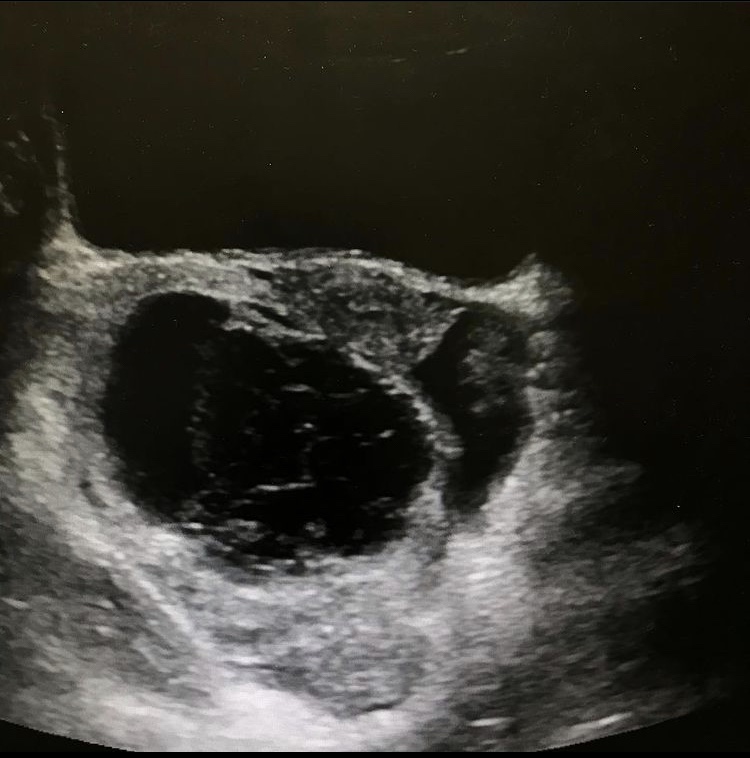

Ovarian torsion

Case #1

Left ovarian torsion with laparoscopic image